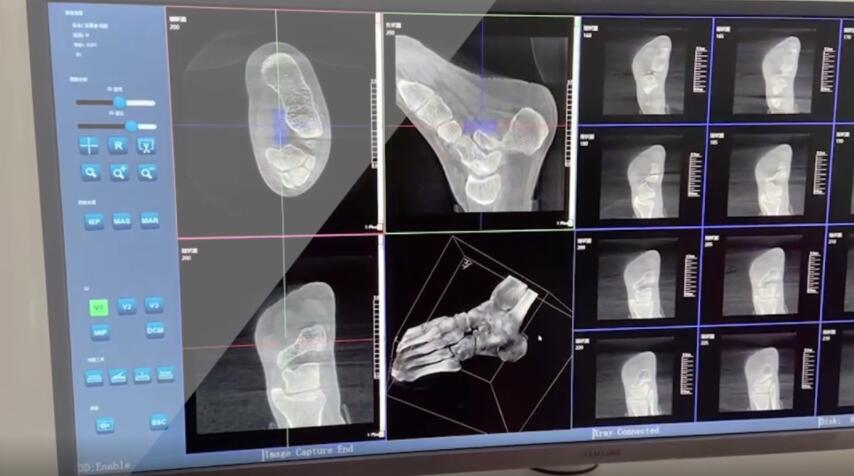

踝關(guān)節(jié)是人體中負(fù)重較大的關(guān)節(jié),也是活動(dòng)度較大的地方,所以對(duì)于足踝部位的關(guān)節(jié)內(nèi)骨折,我們更需要做到“解剖復(fù)位”。對(duì)于這種關(guān)節(jié)內(nèi)的骨折,尤其是踝關(guān)節(jié)內(nèi)部的骨折,不僅需要進(jìn)行X影像平片正側(cè)位的拍攝,由于在二維影像上無(wú)法判斷關(guān)節(jié)面的受損情況,往往還需要進(jìn)行三維影像的檢查。

在術(shù)前,我們需要做三維掃描的CT檢查,我們必須要有CT的片子,還要有三維的重建。

在術(shù)中,我們?cè)趺慈ヅ袛嚓P(guān)節(jié)面平不平整呢?常規(guī)的正側(cè)位影像是不能判斷的。有些醫(yī)生為了準(zhǔn)確的判斷,可能會(huì)選擇做開(kāi)放性的手術(shù),把關(guān)節(jié)暴露出來(lái),在眼睛的直視下判斷關(guān)節(jié)面平不平整。但是關(guān)節(jié)全部打開(kāi),無(wú)疑增加了病人的創(chuàng)傷,而且增加了患者的恢復(fù)時(shí)間。所以如果在術(shù)中我們有三維影像的支持,對(duì)醫(yī)生做手術(shù)而言就會(huì)事半功倍,而且能夠大大的增加手術(shù)準(zhǔn)確度,增加患者術(shù)后的預(yù)后。所以在術(shù)中有三維影像的支持是非常必要的!

三維影像 看透關(guān)節(jié)內(nèi)骨折的“眼睛”